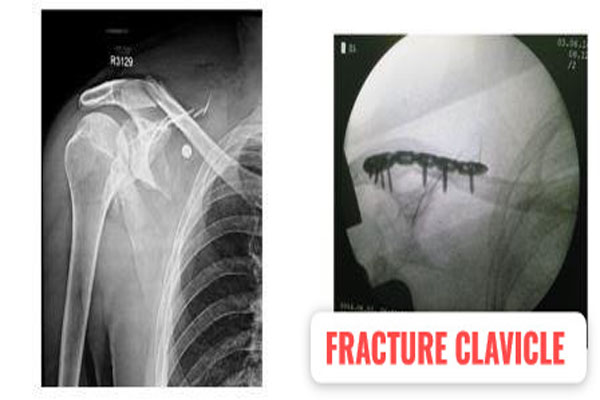

Fracture of bones is commonly handled by almost all orthopaedic surgeons in India. But dealing with comminuted intra-articular fractures (involving joints) is a night mare for most of them. It requires special expertise and experience to deal with such kind fractures. It can involve pelvic acetabular fracture, upper portion of thigh bone ( hip), lower portion of thigh bone ( femur), upper portion of arm bone (humerus head), lower portion of arm bone (humerus), lower portion of forarm bone (lower end of radius) fracture of heel bone, etc. The idea is to maintain the joint (articular) integrity and prevent the permanent loss of movements at that joint. It requires image intensifier (c-arm) to do these surgeries. May be artificial bone or autograft (patient’s own bone taken from iliac bone) to fill in the bone defect/ loss if present. The fracture may take 2- 3 months to heal. Patient may require prolonged physiotherapy to gain near normal range of motion exercises.